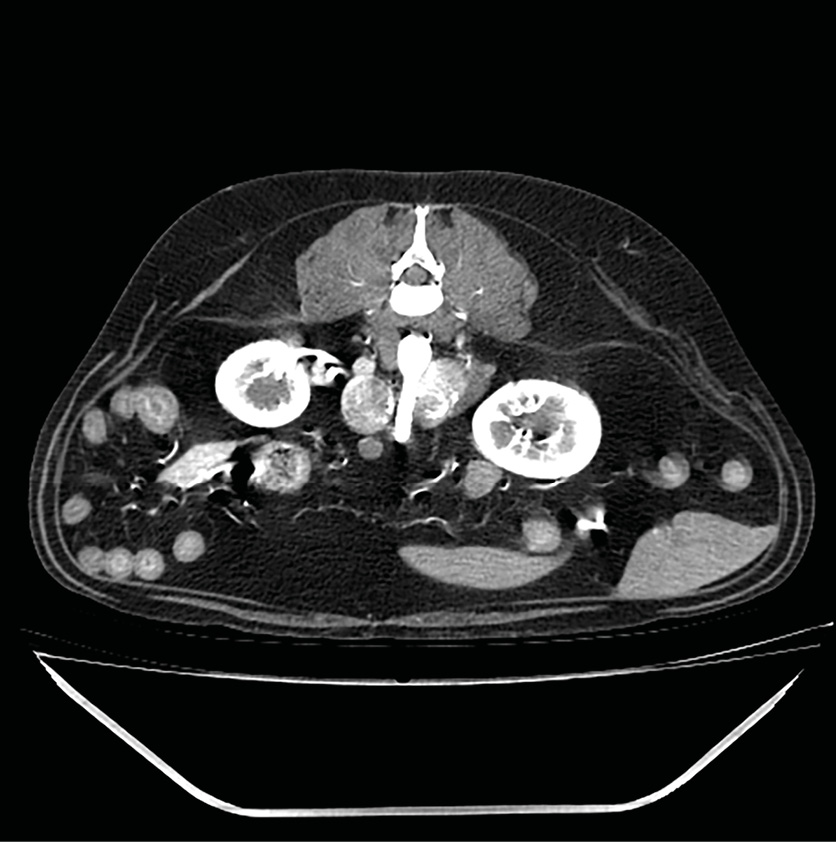

El diagnóstico diferencial de nódulos y masas adrenales incluye hiperplasia adrenal, adenoma, adenocarcinoma, feocromocitoma y, con menor frecuencia, aunque también se han reportado: neuroblastoma, ganglioneuroma, mielolipoma, metástasis, granuloma, hematoma21. Ecográficamente no se puede diferenciar un tumor maligno de uno benigno, pero la presencia de una masa igual o superior a 2 cm de tamaño y/o la observación de invasión vascular deben considerarse criterios de malignidad22 (imágenes 3 y 4).